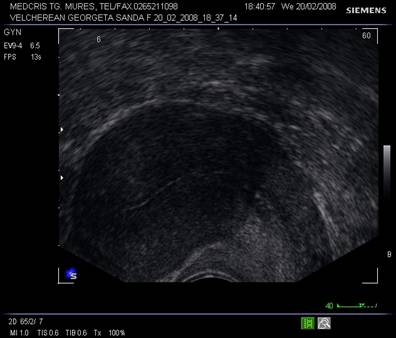

Fig. Nr.358. Uter in sectiune longitudinala, in anteversoflexie

Fig. Nr.359. Sectiune transversala la ecografia transvaginala, la nivelul corpului uterin